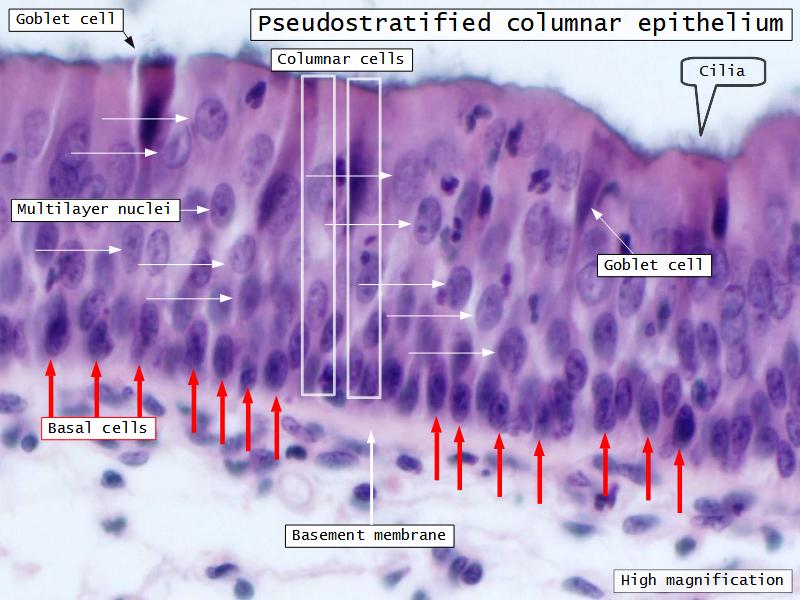

Respiratory epithelium

- Pseudostratified

- Ciliated

- Columnar

- Epithelium with

- 4 Cells

- Ciliated columnar cells

- Non-ciliated columnar cells

- Goblet cells

- Basal cells